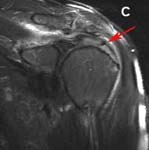

An experienced physician, therapist, shoulder surgeon, or sports medicine surgeon can usually recognize the signs of rotator cuff problems. While the rotator cuff can not be directly visualized on X-rays, there may be subtle signs on the bones of the shoulder joint that can suggest a problem. If suspected, the diagnosis can almost always be made or confirmed using Magnetic Resonance Imaging techniques (MRI). However, many different problems can present with shoulder pain, so a thorough clinical examination by an experienced orthopedic shoulder surgeon is recommended. (See Fig. 3.)

The physical examination and history are a reliable means to diagnose rotator cuff weakness and pain. Many times, persons will have no abnormalities on X-ray (the cuff can not be visualized with x-ray), but MRI is very reliable in confirming a suspected diagnosis. Frequently, and MRI arthrogram will be performed. For this study, a contrast ‘dye’ is injected into the joint just prior to the MRI. This study is nearly 100% accurate in diagnosing a tear. (See Fig. 3)

X-rays may show bony injuries reactions to a dysfunctional rotator cuff tear. Cysts can occasionally be visualized in the region of the cuff insertion at the humerus, the humeral head may migrate toward acromial roof, or bone spurs may develop on the undersurface of this roof. MRI images give cross-sectional pictures of the rotator cuff. Small tears or fraying of the cuff tissue are frequently seen and large and massive tears are easily apprecitated.